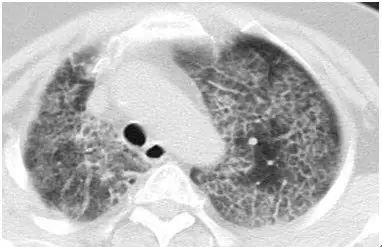

在初期(< 1 cm)往往很纯、密度很低、边界也清晰,这时还不一定是恶性的,可以称为「纯 GGO」。

切除后多证实为腺瘤样不典型增生(AAH,癌前病变)或原位腺癌(AIS,未侵犯周围血管间质、不会转移,5 年生存率 100%),极端情况下也可是微浸润腺癌(MIA,侵犯周围血管间质 < 5 mm,不会转移,切除后 5 年生存率 100%)。

20% 的纯 GGO 在随访过程中病灶会增大或变成混合型 GGO,而 40% 的混合型 GGO 在随访中会增大或实变区增大。

当逐渐长大进展,纯 GGO 的实性成分增加,成为「混合性GGO」。有时,还会出现分叶、毛刺、空泡,胸膜凹陷,血管密集等改变,这时多数已经是恶性了,为浸润性腺癌——可侵犯血管、肺内或全身转移。